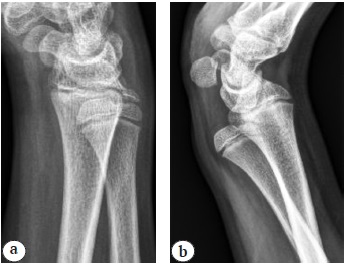

An X-ray functional study (radiography in the site of the ulnar head dislocation) enabled analysis of the change in the position of the ulna in the case of a clinically detectable subluxation/dislocation of the ulnar head, whereas on standard radiographs in the lateral projection, we did not reveal significant changes in the radioulnar distance in the affected limb (Fig. 9).

Fig. 9. X-ray of the wrist joint of a 13-year-old patient with a diagnosis of posttraumatic dislocation of the ulnar head. Instability of the distal radioulnar joint: a — lateral projection; b — X-ray functional examination in the position of dislocation of the head of the ulna (volar type)